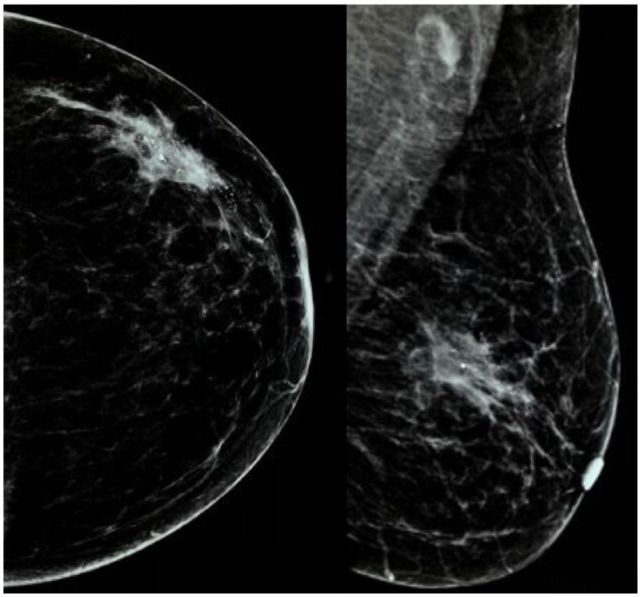

Methods: This was a prospective study conducted between October 1, 2019, and March 31, 2021. Patients with early breast cancer, estrogen and progesterone receptors negative and either Her2 positive or negative, and who were fit to undergo marker placement at the centre of the tumour and to receive third-generation chemotherapy (4 cycles of 3 weekly doxorubicin and cyclophosphamide followed by 4 cycles of 3 weekly docetaxel) were included in the study. Following the enrolment, a tissue marker was placed at the centre of the tumour and appropriate chemotherapy was started. Patients who achieved clinical complete response were subjected to ultrasound-guided vacuum-assisted biopsy (VAB) from the tumour bed before surgery. Pathology results of the VAB and resected specimen were then compared. Descriptive statistics were used in the study.

Results: Eighteen patients were enrolled in the study, with a mean age of 43.6 ± 9.8 years. However, only 10 were eligible for VAB procedure, and sensitivity and specificity were calculated based on the results of these 10 patients only. Vacuum-assisted biopsy showed sensitivity of 50% and specificity of 100% in identifying pCR. Combination of mammography, ultrasonography, and VAB showed sensitivity of 77.8% and specificity of 66.7% in identifying pCR.